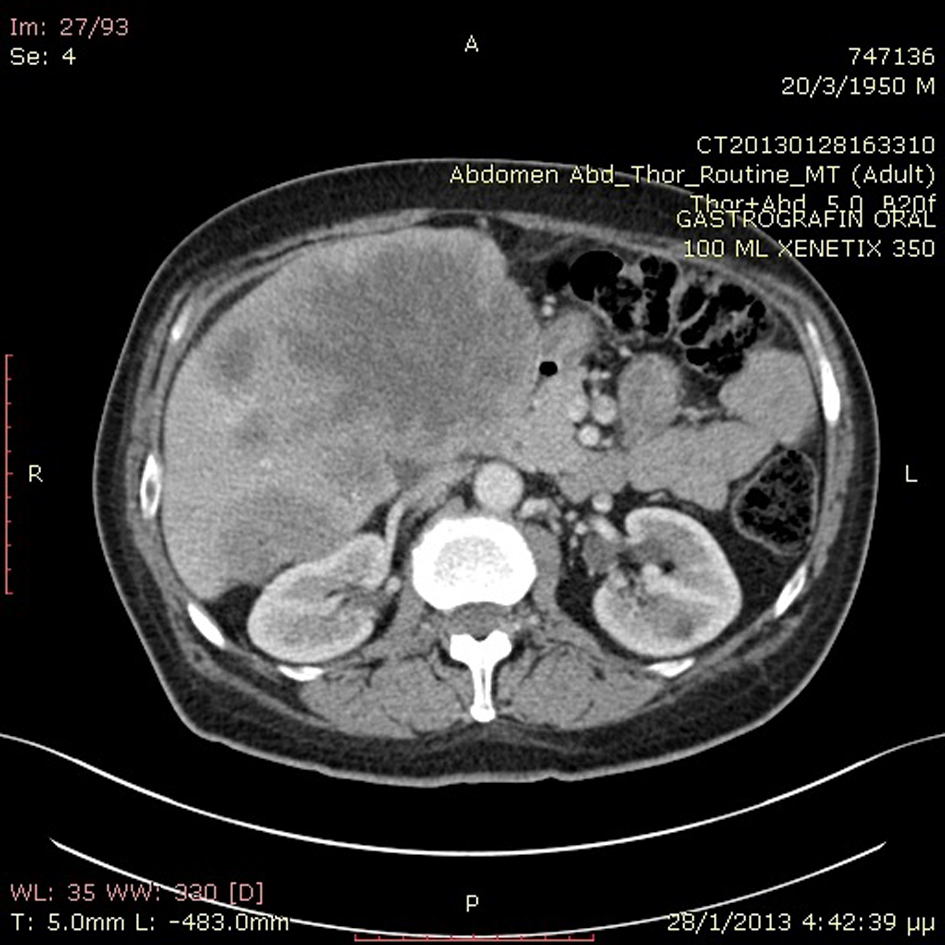

A previously healthy 62-year-old Caucasian male was referred to our department with a 6-month history of diarrhea and weight loss. He underwent colonoscopy which revealed an invasive, hemorrhagic, ulcerated mass of the rectosigmoid area causing obstruction. Serum tumor markers were CEA > 1,500 ng/mL and CA19.9 > 1,200 U/mL. Histological examination of the tumor revealed a G2 grading adenocarcinoma of the colon. CT scans of the thorax and abdomen detected metastatic disease of the lungs and liver (Fig. 1) respectively (stage IVb). Hence, a self-expanding stainless steel stent was successfully endoscopically placed. The patient began systemic therapy with FOLFOX plus bevacizumab. Four months later the stent was obstructed from tumor ingrowth and a new stent was placed (stent to stent) while a subsequent CT scan confirmed progression of disease. At that time, patient presented a cystic lesion of the scalp at the right temporal area (Fig. 2). Histological analysis of the excised lesion of the scalp revealed a metastatic medially differentiated adenocarcinoma, most likely originating from the large bowel, which infiltrated the subcutaneous tissue and the skin (Fig. 3). A palliative care was followed as he had rapid physical decline and he was discharged home under a nursing care where he died 2 weeks later.

![]() Click for large image | Figure 1. Abdominal CT scan revealed metastatic liver disease. |